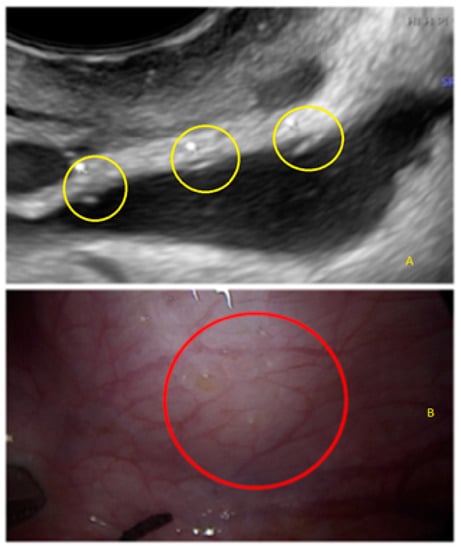

- The presence of hyperechoic foci (we called this a “pearl”).

3.2. Cystic Multiple Separate Lesions